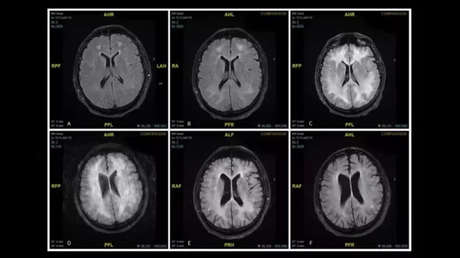

Los médicos del hospital Mater Dei de Malta han hecho públicas unas resonancias magnéticas del cerebro de un hombre de 45 años consumidor habitual de cocaína que muestran el daño provocado por la sustancia. El caso ha sido descrito en la revista British Medical Journal.

Después de diferentes exámenes, los especialistas determinaron que el hombre había sufrido un efecto secundario muy inusual, pero potencialmente peligroso, inducido por el narcótico y denominado leucoencefalopatía. De acuerdo con los médicos, el trastorno se puede presentar de distintas maneras, incluido un nivel alterado de la conciencia, confusión, lenguaje y visión alteradas, fiebre o espasticidad. Los registros de los escáneres mostraron la aguda degeneración de la materia blanca de su cerebro.

Tras dos semanas de tratamiento con esteroides, un intercambio de plasma y anticuerpos el paciente comenzó a mostrar mejoría y fue trasladado a una clínica de desintoxicación. Un año después, los exámenes determinaron que su capacidad cognitiva funcionaba de forma normal, aunque el cerebro seguía mostrando signos de los daños causados por la droga.